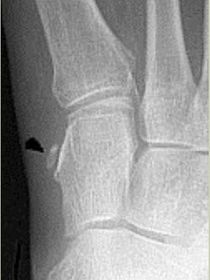

What type of fracture is this? | Avulsion fracture |